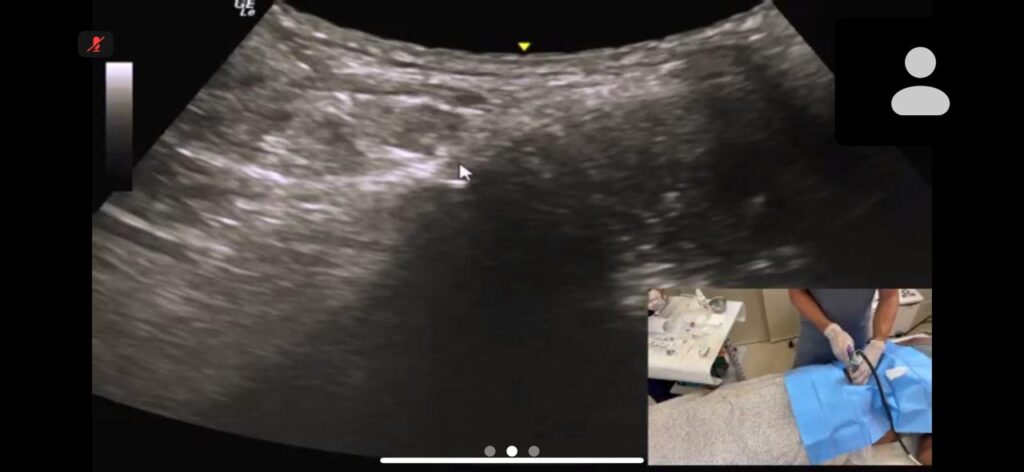

Esse concentrado é então utilizado no tratamento da lesão, com aplicação guiada por imagem para maior precisão.